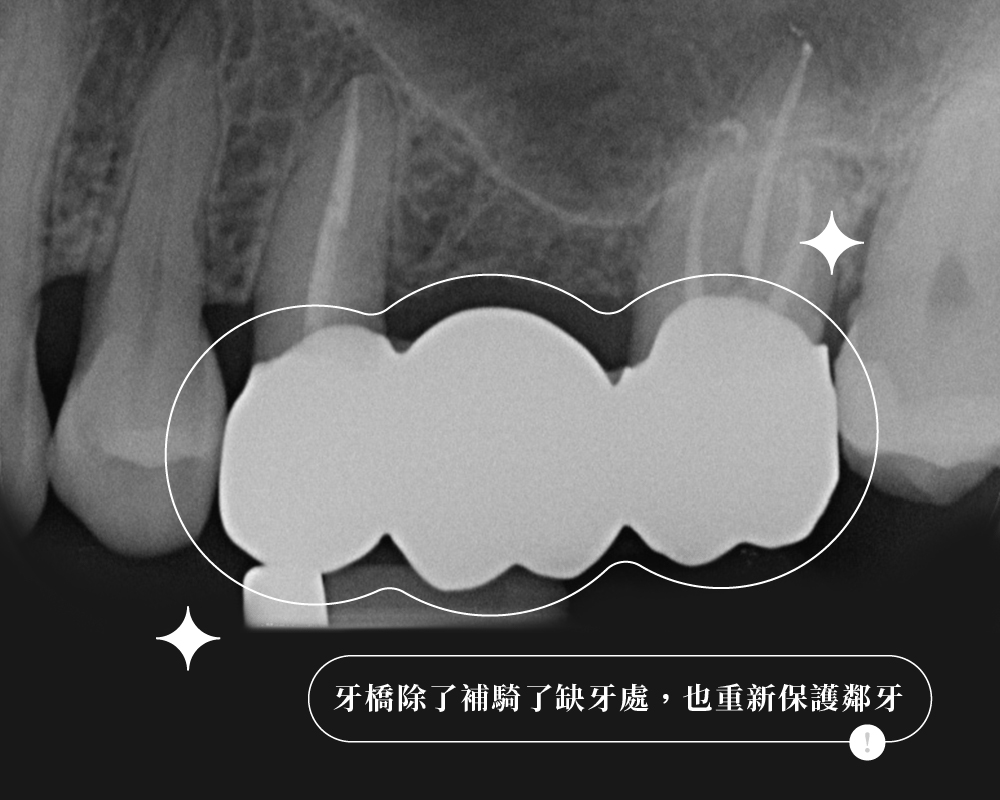

2. 鄰牙本身健不健康,決定了這座「橋」該不該搭

牙橋有點像搭橋:中間缺牙的位置是橋面,前後兩顆牙則像橋墩。

橋墩本來就老舊、破損需要補強,把它們一起納入設計,未必是壞事

簡單來說,牙橋不是不能做,關鍵在於前後兩顆牙值不值得一起被納入設計。

缺牙後能不能做牙橋,從來不是只看「補不補得上」,而是要看這座橋在長期使用下,能不能承受得住。